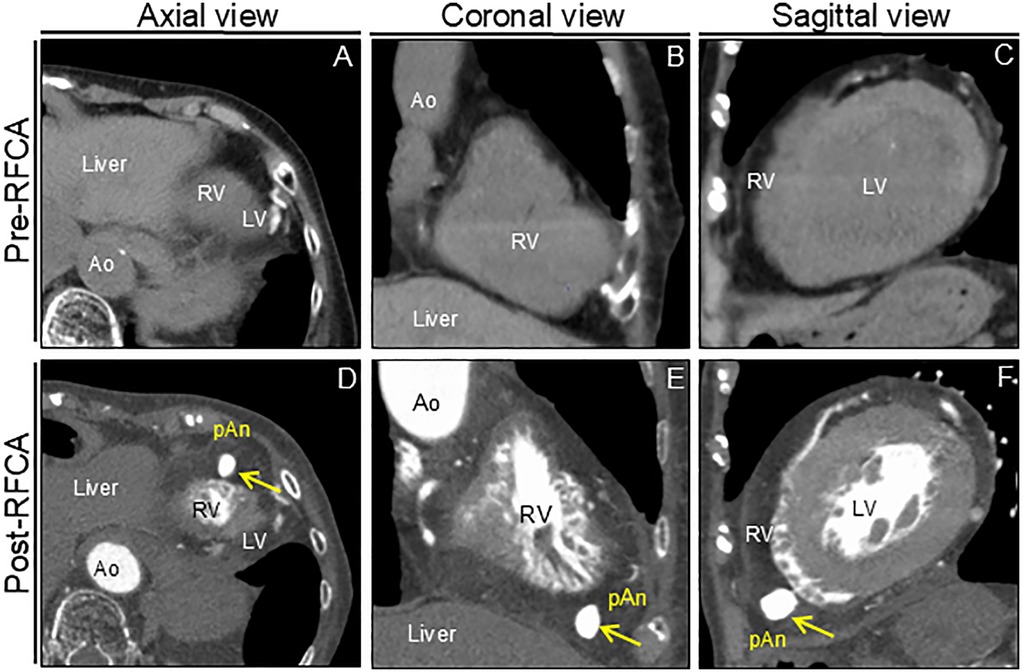

An 88-year-old woman was admitted with symptomatic paroxysmal supraventricular tachycardia that had persisted for three years. The patient had a history of severe aortic stenosis for which transapical transcatheter aortic valve replacement was performed seven years ago. Her initial vital signs were blood pressure of 79/60 mmHg and heart rate of 164 beats/min. The physical examination findings were unremarkable. Laboratory test revealed elevated serum level of brain natriuretic peptide (171.6 pg/ml, reference: <18.4 pg/ml). Electrocardiography revealed narrow QRS tachycardia with a short RP (Supplementary Figure S1A). Tachycardia was terminated with rapid intravenous administration of adenosine triphosphate (Supplementary Figure S1B). However, the patient experienced frequent paraoxymal supraventricular tachycardia episodes. Echocardiography revealed no structural or functional heart abnormalities (Figure 1A; Supplementary Video S1). Unenhanced computed tomography scans showed no biventricular abnormalities suggestive of myocardial infarction or aneurysm. An electrophysiological study was performed four days after admission. Catheters were placed in the high right atrium, the His bundle region, coronary sinus, and right ventricular (RV) apex. Premature ventricular contractions frequently occurred during RFCA, and, hence, the RV pacing catheter was held tightly to avoid the unintended catheter movement. Based on the electrophysiological study, slow/fast atrioventricular nodal reentrant tachycardia was diagnosed. Subsequent successful anatomical slow-pathway ablation was performed according to standard techniques (Figures 1B,C). We excluded any complications, including cardiac tamponade, on postprocedural echocardiography. Follow-up echocardiography revealed RV apical outpouching on postprocedural day 2 (Figures 1D–F; Supplementary Video S2). The patient was asymptomatic, and her vital signs were stable. Physical examination and electrocardiographic findings were unremarkable (Supplementary Figures S1C,D). Follow-up laboratory tests were close to normal. Differential diagnoses of ventricular outpouching include true aneurysms and pseudoaneurysms. Cardiac computed tomography angiography (CCTA) further characterized the morphology and features of the RV apical outpouching (Figures 2A–D). Note the presence of contrast-filled RV outpouching at the apex that protruded during systole, with a maximum diameter of 12.1 mm and a narrow orifice of 1.5 mm with an orifice-to-maximum diameter ratio of 12.4%, suggestive of RVP. CCTA revealed normal coronary arteries (Figures 2E,F). Pericardial effusion was not observed. A detailed review of the computed tomography images confirmed the absence of RVP before the RFCA procedure and its presence after the procedure (Figure 3). Given the temporal relationship between RFCA and the occurrence of RVP without any other identifiable cause, a final diagnosis of iatrogenic RVP was made. After multidisciplinary discussion, taking into consideration that a ventricular pseudoaneurysm is susceptible to cardiac rupture, the patient underwent urgent surgical repair of the RVP. No bleeding was observed in the pericardial sacs. There was no evidence of pericarditis, intrapericardial bleeding, or cardiac rupture except for a slight bulge at the RV apex. Epicardial echocardiography was used to identify the pseudoaneurysm, as such pseudoaneurysm was difficult to identify by visual examination. Subsequent vertical mattress suture repair with Teflon-felt reinforcement was performed for the RVP. The patient's postoperative course was uneventful, and she remained asymptomatic at the one-year follow-up (Supplementary Figure S2).

Figure 3. Computed tomography images before and after RFCA. Preprocedural unenhanced computed tomography images confirm normal right ventricular anatomy (A–C). Postprocedural cardiac computed tomography angiography images reveal apical outpouching of the right ventricle (arrows) (D–F). Ao, aorta; LV, left ventricle; pAn; pseudoaneurysm; RFCA; radiofrequency catheter ablation; RV, right ventricle.